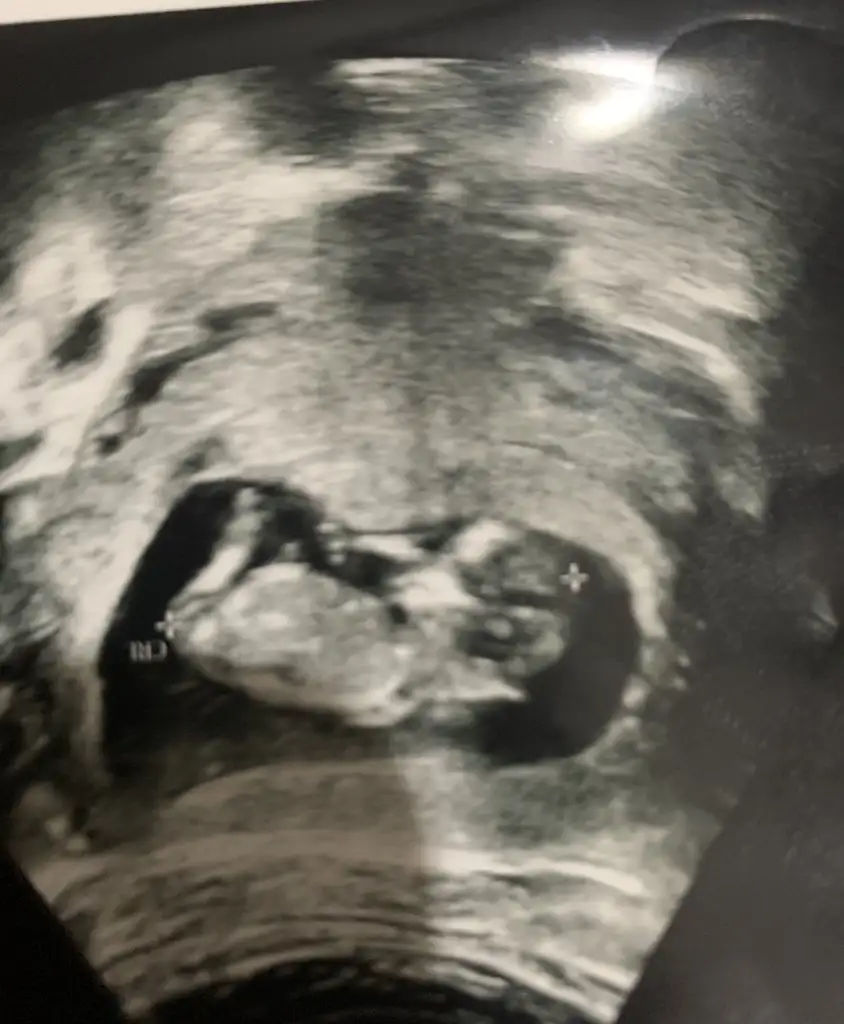

Cinsiyet tahmini yapabilir misiniz :) 9+5

Bana da öyle geldi canımm ama hayırlısı bakalım 🙈😂

Aminn kuzum hayırlısı olsun inşallahhh cinsiyet hiç önemli değil yeterki sağlıklı olsunlar da merak ediyoruz işte 😂 haftaya kontrolum var benimde bakalım görünecek mii 😊 geçen instagram da amerikali bi bayana rastladım 10. Haftada cinsiyet paylaşmış şok oldum turkiyede biraz daha gec bakiyorlar galiba 🤔😊